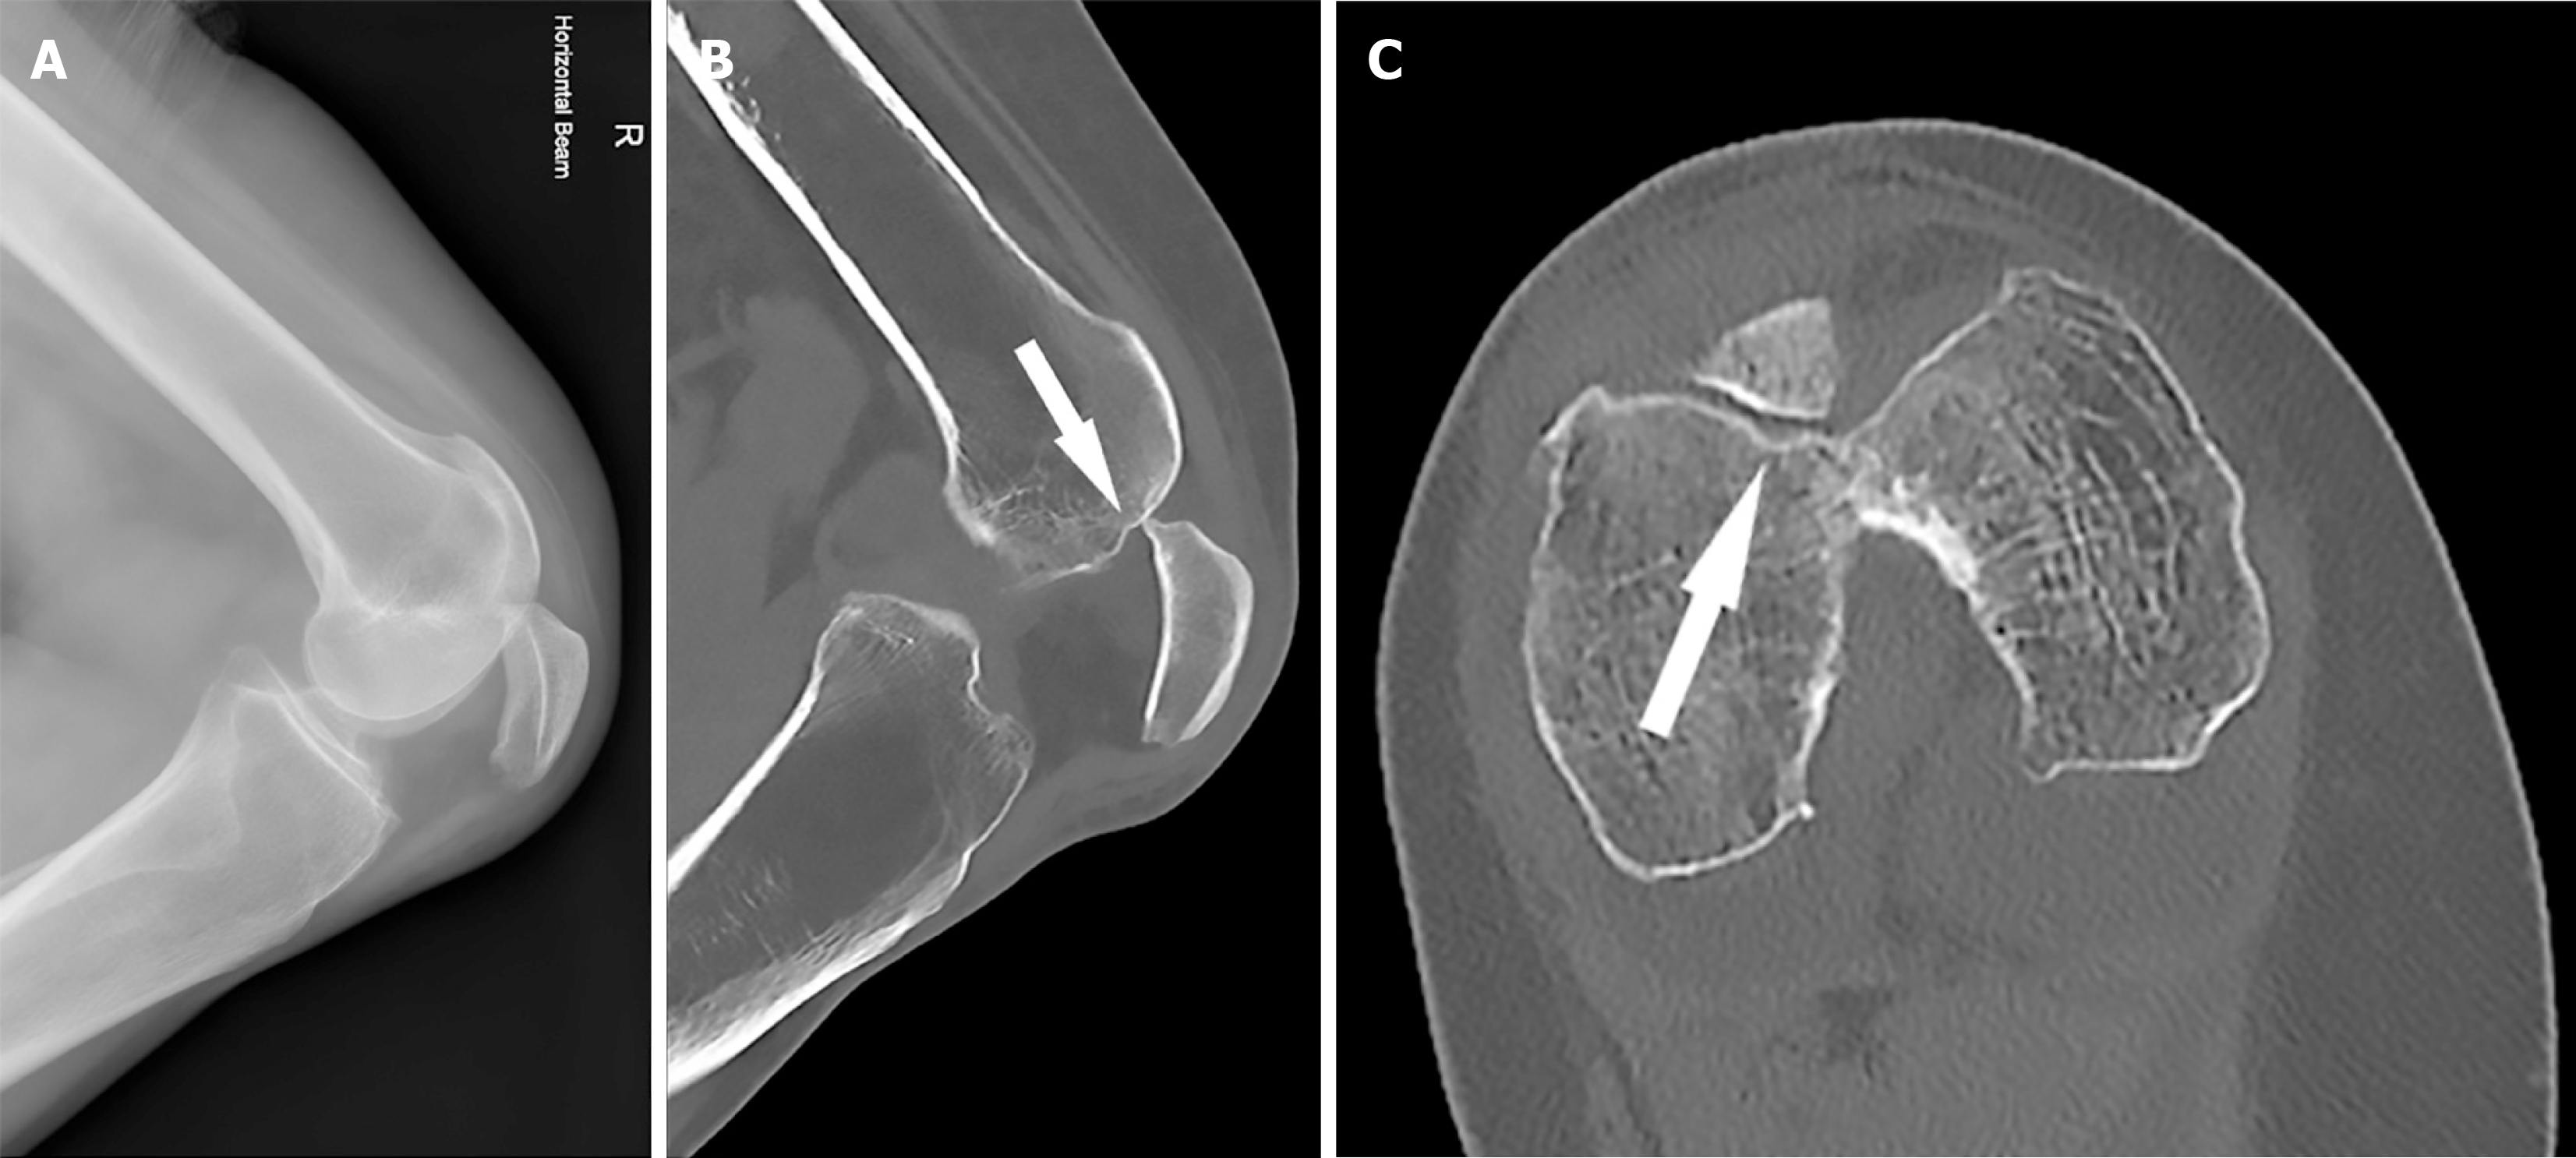

Figure 2 Preoperative magnetic resonance imaging.

A: Mildly depressed femoral trochlear osteochondral injury (white arrow) with a concertinaed patella tendon with heterogenous signal equivocal for a partial tear; B: Small femoral trochlear osteochondral injury slightly lateral of the midline (white arrow).